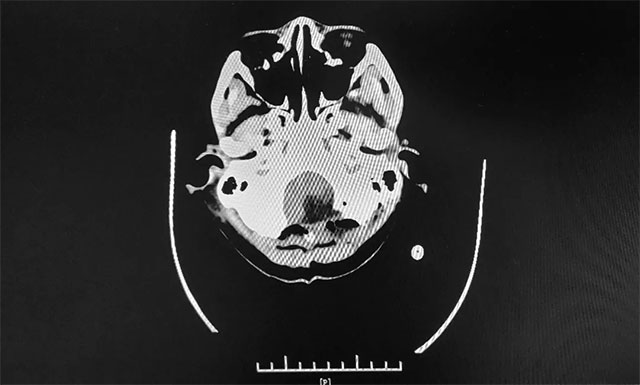

▲ 術(shù)前MR影像:左側(cè)小腦半球及小腦蚓部占位

頭顱磁共振顯示:小腦蚓部、累及左側(cè)小腦半球“大囊小壁結(jié)節(jié)”樣占位,壁結(jié)節(jié)富血供,伴少量陳舊出血,幕上輕度腦積水,左側(cè)扁桃體輕度下疝。潘仁龍主任、李士其教授、吳治群博士會(huì)診后考慮為顱內(nèi)海綿狀血管瘤,這個(gè)血管瘤經(jīng)常周期性滲血,每次病發(fā)時(shí)便會(huì)壓迫小腦神經(jīng)系統(tǒng),輕則影響小腦功能,造成眩暈、惡心等癥狀;重則血管瘤破裂,直接危及生命。手術(shù)指征明確,需及時(shí)手術(shù)。